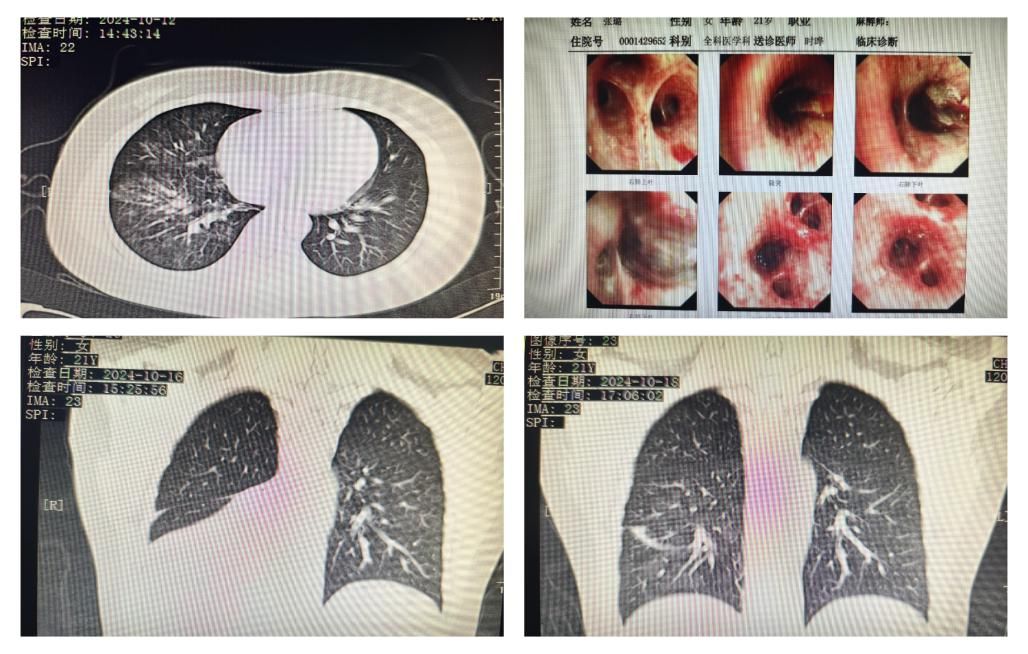

患者为苏州游客,2024年10月11日食用牛油果时剧烈呛咳,随后出现胸部隐痛,未予重视。次日出现咳血,立即就诊于黑料网。门诊电子喉镜检查未见明显异常,胸部CT提示右肺中下叶炎症,以“未分化疾病-咯血原因待查”入住全科医学科。患者4年前诊断克罗恩病,长期应用免疫抑制剂英夫利昔单抗治疗。入院经抗感染、止血治疗,患者仍有间断咯血,伴一过性呼吸困难及血氧饱和度降低,时晔、徐博主任团队详细询问病史及认真阅片,患者影像学特点及感染相关指标正常,不支持一般感染性肺炎的诊断,安排第三天复查胸部CT,发现右肺下叶肺不张。结合发病时情况及支气管解剖特点,高度怀疑气管吸入异物,病情紧急,需要尽快支气管镜检查明确右下肺不张病因。此时已临近下班,郭伟主任恰好在病房,及时联系呼吸与危重症一科陈瑞琳主任医师进行会诊,指导值班医生行次日支气管镜检查准备,并和家属充分知情告知检查必要性及可能风险。

次日,在时晔主任及雷鸣主管医生陪同下,陈瑞琳主任医师进行支气管镜检查,发现患者右肺下叶管口条索状异物,完全阻塞右肺下叶支气管,活检时发现异物质软,且与气道壁嵌合,反复使用活检钳及异物篮均不能顺利取出。患者因治疗时间长剧烈咳嗽、不耐受治疗,随急诊请胸外科戴云副主任医师、麻醉科徐瑞芬主任医师到支气管室会诊配合,经过液氮冷冻、网篮及反复抽吸后,取出数条支气管树状异物,似为牛油果泥与凝血块混合物,此时右肺下叶管腔完全通畅。术后次日复查胸部CT,患者右下肺不张明显改善,继续药物抗感染止血等治疗,患者病情好转,未再咳血,双肺呼吸音正常,血氧饱和度99%,于10月21日顺利出院。